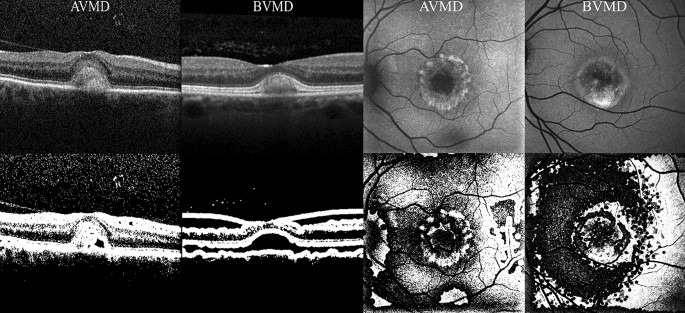

Image processing was performed using an open-source image processing software (ImageJ, NIH, Bethesda, MD). All images were converted in 8-bit mono-dimensional images. Both OCT B-scan and BAF images were than elaborated using an auto local thresholding method for binarization. Local thresholding is a group of procedures in which the threshold for each pixel is computed in relation to the image characteristics within a window of radius r (in pixel units) of pixels around it. Pixels whose luminance is above the locally calculated threshold are always shown as white (255 intensity). In particular, BAF images were elaborated with a contrast-based local thresholding method, which sets the pixel value to either white (255) or black (0) depending on whether its current value is closest to the local maximum or minimum respectively (threshold in this case is represented by the median of the local luminance) (see Fig. 1)26. By contrast, OCT images were modified using a mean-based method, that selects the threshold for binarization as the mean of the local greyscale distribution (threshold in this case is represented by the mean of the local luminance) (see Fig. 1)26. For both BAF and OCT images a kernel radius of 8 was applied. The same blinded human graders that performed binary image classification (BVMD or AVMD) of unprocessed images were then asked to perform twice again the same task, this time based on B-scan OCT and BAF processed images, respectively.

OCT (left quadrant) and BAF (right quadrant) images before (first row) and after (second row) image processing. BAF blue autofluorescence, OCT optical coherence tomography.

Deep learning versus human classification using BAF images

Among the 631 available OCT images, both the unprocessed-images-based and the processed-images-based deep learning classifier were trained with 429, validated with 76 and tested with 126 images (69 BVMD images and 57 AVMD images). The performances of the human-based methods (considering either processed or unprocessed images) were evaluated on the same set of 126 images. Human-based evaluation showed a sensitivity of 66.7%, a specificity of 68.4%, a PPV of 71.9% and a NPV of 62.9% (AUROC 0.662, CI 0.657–0.684), with a moderate agreement between graders (k = 0.581, CI 0.563–0.596). OCT processed images were characterized by hyporeflectivity of the vitelliform deposit in the case of BVMD and hyperreflectivity with high internal inhomogeneity in the case of AVMD (see Fig. 1). Diagnosis attribution based on processed images was characterized by a good inter-grader agreement (k = 0.682, CI 0.645–0.699), a sensitivity of 75.4%, a specificity of 77.2%, a PPV of 80.6% and a NPV of 72.1% (AUROC = 0.741, CI 0.718–0.757). The deep learning method based on unprocessed images showed a sensitivity of 88.4%, a specificity of 89.5%, a PPV of 91.0% and a NPV of 86.4% (AUROC = 0.867, CI 0.853–0.881). Lastly, the deep learning method based on processed images was characterized by a sensitivity of 91.3%, a specificity of 91.2%, a PPV of 92.6% and a NPV of 89.6% (AUROC = 0.893, CI 0.882–0.911) (see Table 2, Fig. 3). Relevant features for classification were highlighted using gradCAM method on each of the four deep learning classifiers (see Fig. 4).

Image processing of BAF images facilitated the distinction between the two entities to human graders, leading to a significantly higher correspondence to ground truth diagnosis compared to human-based analysis of unprocessed images. Human-based distinction of BAF processed images was based on the presence of hypoautofluorescent halos of variable size surrounding BVMD lesions that were not present in unprocessed images (see Fig. 1). Given the fact that processed images were the result of a local contrast-based filtering, this elaboration might have enhanced subtle local parafoveal decrease in autofluorescence. This, in turn, might be reflecting a disfunction in RPE metabolism involving a much larger area of the posterior pole than the one visible at raw BVMD BAF images. By contrast, AVMD might be characterized by a much more localized type of involvement. The hyperautofluorescence of the central lesion in both BVMD and AVMD is allegedly due to the subretinal deposition of lipofuscin generated by RPE disfunction in the turn-out of the photoreceptors’ outer segments. The surrounding hypoautofluorescent areas evidenced by image processing in BVMD might highlight areas of lower activity of the RPE that still retain enough functionality to avoid lipofuscin accumulation6. CNN analysis of both processed and unprocessed OCT images showed very high adherence to ground truth classification (respectively 91.3% and 88.4% sensitivity). GradCAM visualization highlighted the outer retinal layers overlying the center and the borders of the vitelliform lesion as significant discriminative regions (see Fig. 4). Interestingly, Ferrara et al.33 pointed out the thinning of the outer nuclear layer at the margins of the lesion and the thinning of the photoreceptors complex at the top of the lesion as frequent characteristics in OCT images of BVMD at vitelliform stage. The human-based analysis of OCT images also showed significantly higher correspondence to ground truth reference when performed on processed images (75.4% sensitivity versus 66.7% in the analysis of unprocessed images). Processed OCT images of BVMD fovea showed a dark appearance in correspondence to the vitelliform lesion while AVMD lesions appeared dishomogeneous and prevalently white (see Fig. 1). It should be kept in mind that these differences are the result of a processing mechanism aimed at enhancing the relationship between adjacent pixels. In this case, the dark appearance of pixels within the lesion is the result of a luminance that is below the threshold represented by the median luminance value within a radius of 5. This could be the result of even small luminance differences between adjacent surfaces, that are in this specific case the deposit’s material and the RPE/photoreceptors. The dark appearance could in fact not be interpreted as hyporeflectivity of the lesion but as a relative difference between the material and the adjacent surface which is homogeneous within the deposit and is not present in the case of AVMD. When comparing the performance of human interpretation of BAF and OCT images, it appears that humans performed better in classifying OCT images than BAF images before the application of the image processing method (p = 0.025, see Table 4). By contrast, classification performance of human graders was better when evaluating processed BAF images compared to processed OCT images. To conclude, deep learning methods on both processed and unprocessed BAF and OCT images proved to be highly effective in the distinction between early stage BVMD and AVMD. The application of this method could avoid the use of extensive evaluation and the need for genetic testing. The fact that both groups were composed of working-age patients gives an added value to the potential information deriving from a correct early diagnosis. Lastly, the multicentric nature of the study and the availability of an external set of images to perform testing should be mentioned among the strengths of the article. By contrast, limitations include the retrospective nature of the analysis and the mild asymmetry of the samples.